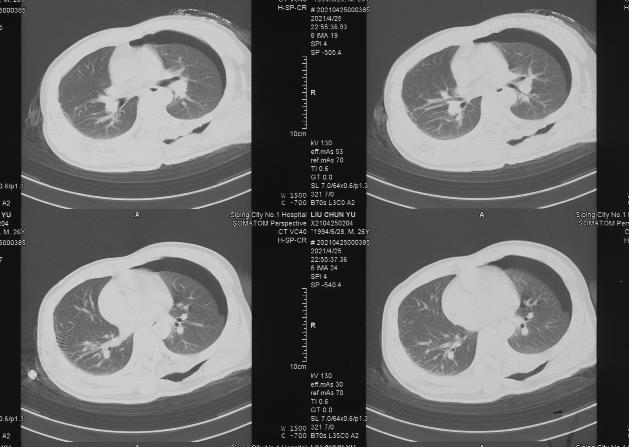

2021年4月25日21:27及22:55两次CT示:左侧腋胸背部皮下积气、积液,左侧少量气胸,左侧胸腔少量积液,肺组织轻度萎陷,22:55较21:27肺组织萎陷程度略有增加,但均未达30%;其右侧肺组织及胸腔未见明显外伤性改变。

2021年5月2日CT示:左肺术后改变,左肺轻度压缩,左侧胸腔少量积液,引流管在位。

2021年5月6日、5月29日CT示:左侧胸腔积液、积气已吸收,肺组织复张,左肺术后改变。

2021年8月27日CT示:左肺术后改变,左肺下叶背段少许条索状纤维灶。